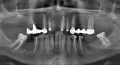

Справа внизу отсутствуют 5 и 6 зуб. 7 зуб запломбирован, 4 зуб перед подготовкой к протезированию перепломбировали за верхушку пастой на основе формальдегида, долго было больно накусывать. Спустя 9 месяцев его перепломбировали с еще большим выводом материала за верхушку (как мне сказали, горячей гуттаперчей). После повторной перепломбировки прошло 7 месяцев.

Сейчас на 4 зубе стоит временно металлокерамическая коронка, отрезанная от несостоявшегося моста-протеза. Зуб не болит, но бывает больно накусывать. Керамический мост плохо держался при многочисленной временной фиксации и давал большую ощутимую нагрузку на 4 зуб. 3 зуб (клык) абсолютно здоров, не хотелось бы его обтачивать. Импланты по нескольким причинам исключаю.

Что касается конструкций, я бы рекомендовал резекцию верхушки корня, тем самым сохранив зуб и восстановив мостовидную конструкцию 4-7 зубов.

В идеале, конечно, имплантация двух зубов и установка коронок на опорные (4, 7).